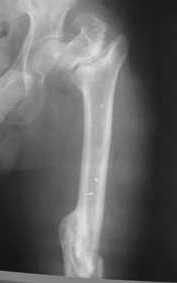

Уважаемые коллеги! Нужен совет.Больной Х., 21 год, ДЗ: ложный сустав вертельной области правого бедра.

Травма 8 мес. назад, ДТП, получил закрытый межвертельный перелом правого бедра. Лечился в городской больнице одного из городов-спутников г. Караганды скелетным вытяжением в течение 3 недель, затем кокситной гипсовой повязкой 2 мес. В настоящее время имеется укорочение конечности на 7 см, умеренная боль в вертельной области; ходит без костылей, полностью нагружая больную конечность, при нагрузке отмечается смещение дистального отломка проксимально примерно на 1,0 см.; объем движений в коленном суставе сохранен; при пальпации отломков боли нет, умеренная патологическая подвижность. Планируем внеочаговый остеосинтез спице-стержневым аппаратом, дистракция до восстановления длины бедра, вторым этапом остеосинтез стержнем Гамма. Есть надежда, что на дистракции пойдет сращение и у больного хватит терпения завершить лечение в аппарате.

Виктор! Судя по снимкам,укорочение не более 2-3 см (даже линия Шентона сохранена). При таком укорочении дистракционный остеосинтез аппаратом внешней фиксации на конкретном сегменте,действительно представляется агрессивным.Может быть,как предлагает D.Kuldjanov,ограничиться предоперационным скелетным вытяжением и после рентгенконтроля использовать Blade Plate или Гамму с губчатой аутопластикой.Возможна миотомия приводящих мышц.Смещение не столь велико,чтобы его форсированное устранение грозило неврологическими осложнениями.Даже остаточное укорочение в пределах 1см вряд-ли усложнит операцию и существенно повлияет на исход.Учитывая статус клиники,для пациента не менее важны комфортность в послеоперационном периоде,возможность полноценно жить и работать в период реабилитации, максимальное снижение вероятности послеоперационных осложнений.А этим условиям аппарат Илизарова не отвечает.

Если судить по снимкам, то укорочение кажеться не критическим, но обьективно и на 3D - укорочение на 6-7 см.